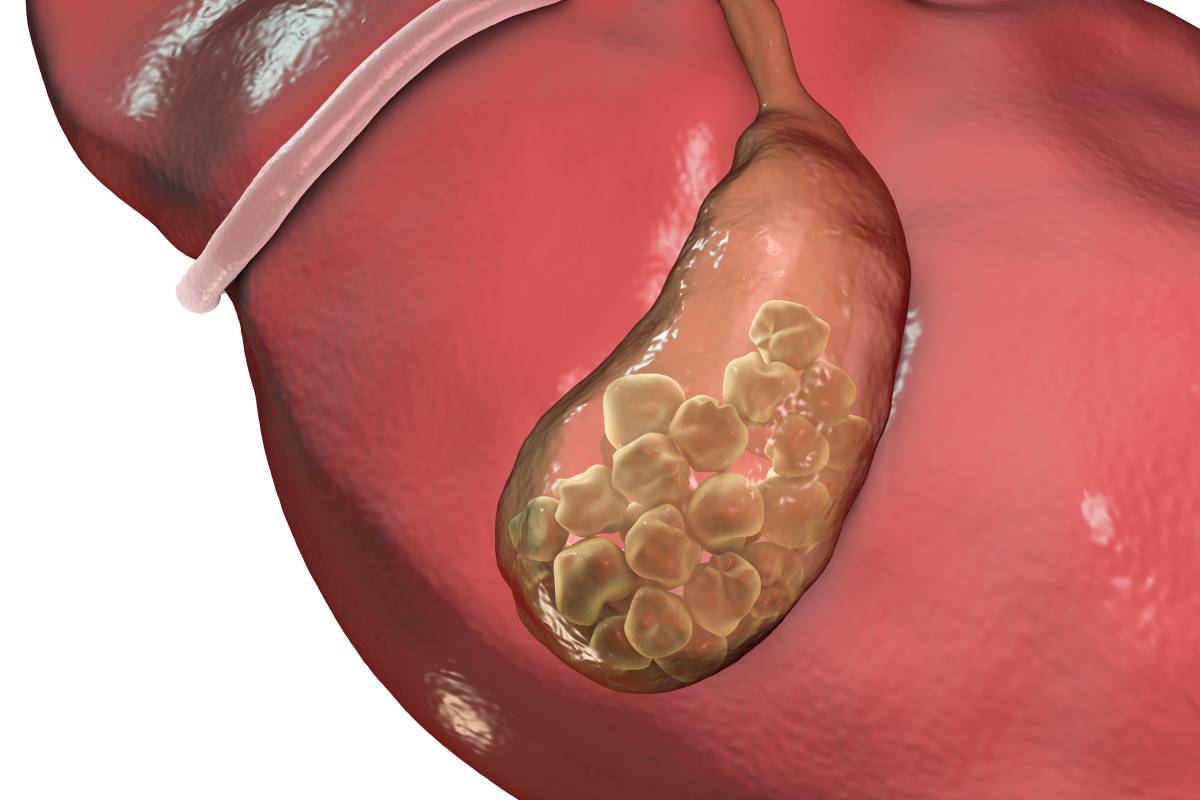

现如今,很多人得过或听过结石。结石的形态也千奇百怪,有泥沙样的,有圆形的,有不规则的。

结石形成的部位也是五花八门,有胆结石、肝结石、肾结石、膀胱结石、胃结石等。

但是以胆结石和泌尿系统结石为多见,而无论是两者中的哪一种,湿热都是结石形成的关键因素。

胆为“腑”,是空腔,内藏胆汁。肝和胆是一对“好兄弟”,也就是中医讲的表里关系。

若肝气不舒,则胆汁不能按时排泄,郁积体内而化热,湿热煎灼胆汁,由此产生“石头”;

或者由于喜食油腻,产生湿热,阻滞于肝胆,煎灼胆汁,也能形成结石。酷似通过暴晒来从海水中获取食盐的过程。

胆结石会产生右上腹疼痛,以及恶心呕吐,口渴舌干,高热畏寒,不思饮食等症状,四诊常见舌苔黄腻,小便色黄,大便秘结,脉弦数。